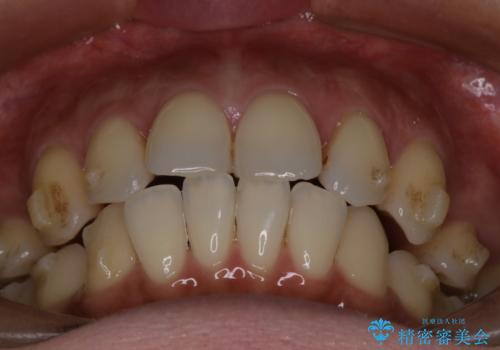

インビザラインにて抜歯矯正を行うと、高頻度で奥歯が咬み合わなくなります。

また、抜歯スペースに向けて奥歯が移動する際、必ず傾斜して移動するため、仕上がりの咬み合わせはワイヤー矯正と比べて明らかに劣ります。

抜歯スペースが閉じてからも咬みにくさ改善のためマウスピース矯正を継続するため、治療期間は長期化します。